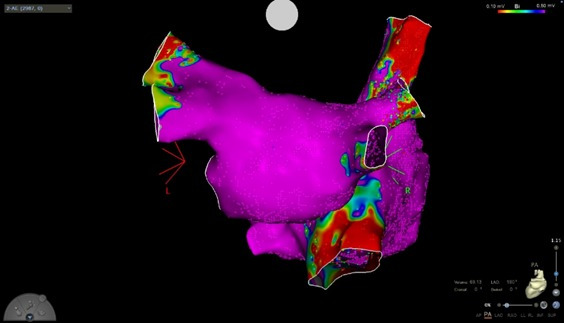

O político deve passar por novos exames neste sábado, 30. Segundo o boletim, o ex-governador estava internado devido a um quadro de “flutter atrial”. Trata-se de um funcionamento irregular do ritmo cardíaco. É caracterizado por sintomas como palpitação e, às vezes, fraqueza, intolerância a esforço e dispneia.

O ex-governador de Goiás Marconi Perillo (PSDB), internado desde a última quarta-feira ,27, no Hospital Sírio-Libanês, em São Paulo, foi submetido a um procedimento médico para tratar arritmia cardíaca na noite de sexta-feira 29.

De acordo com o boletim médico divulgado pelo hospital, o procedimento ocorreu com sucesso e não teve intercorrências. Veja abaixo:

O político deve passar por novos exames neste sábado, 30. Segundo o boletim, o ex-governador estava internado devido a um quadro de “flutter atrial”. Trata-se de um funcionamento irregular do ritmo cardíaco. É caracterizado por sintomas como palpitação e, às vezes, fraqueza, intolerância a esforço e dispneia.